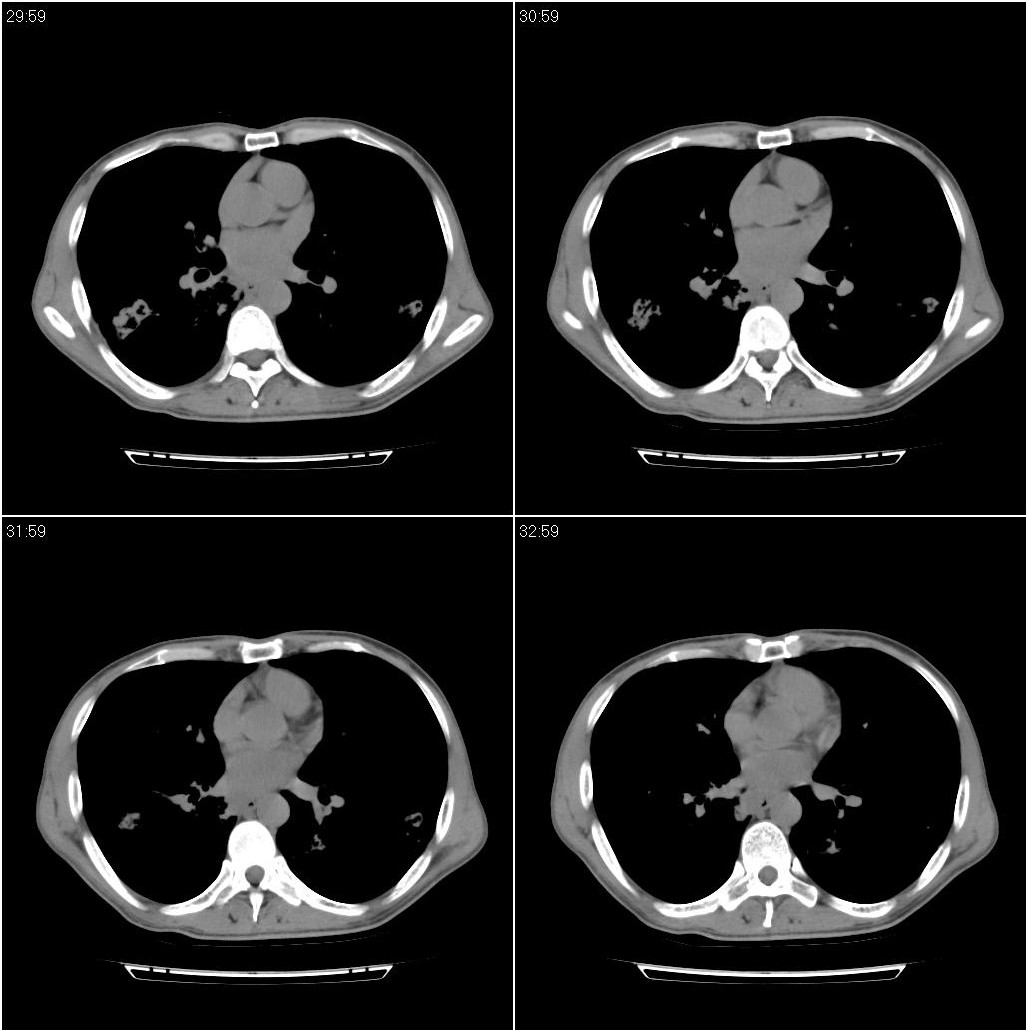

标题: CT23980:男性,47岁。近来咳痰、咳血,血沉增快(40左右),

男性,47岁。近来咳痰、咳血,血沉增快(40左右),痰中未检出结核杆菌。

两肺继发性肺结核并多发性结核球形成,部分病灶内空洞形成。

符合继发性结核表现部分空洞形成并播散